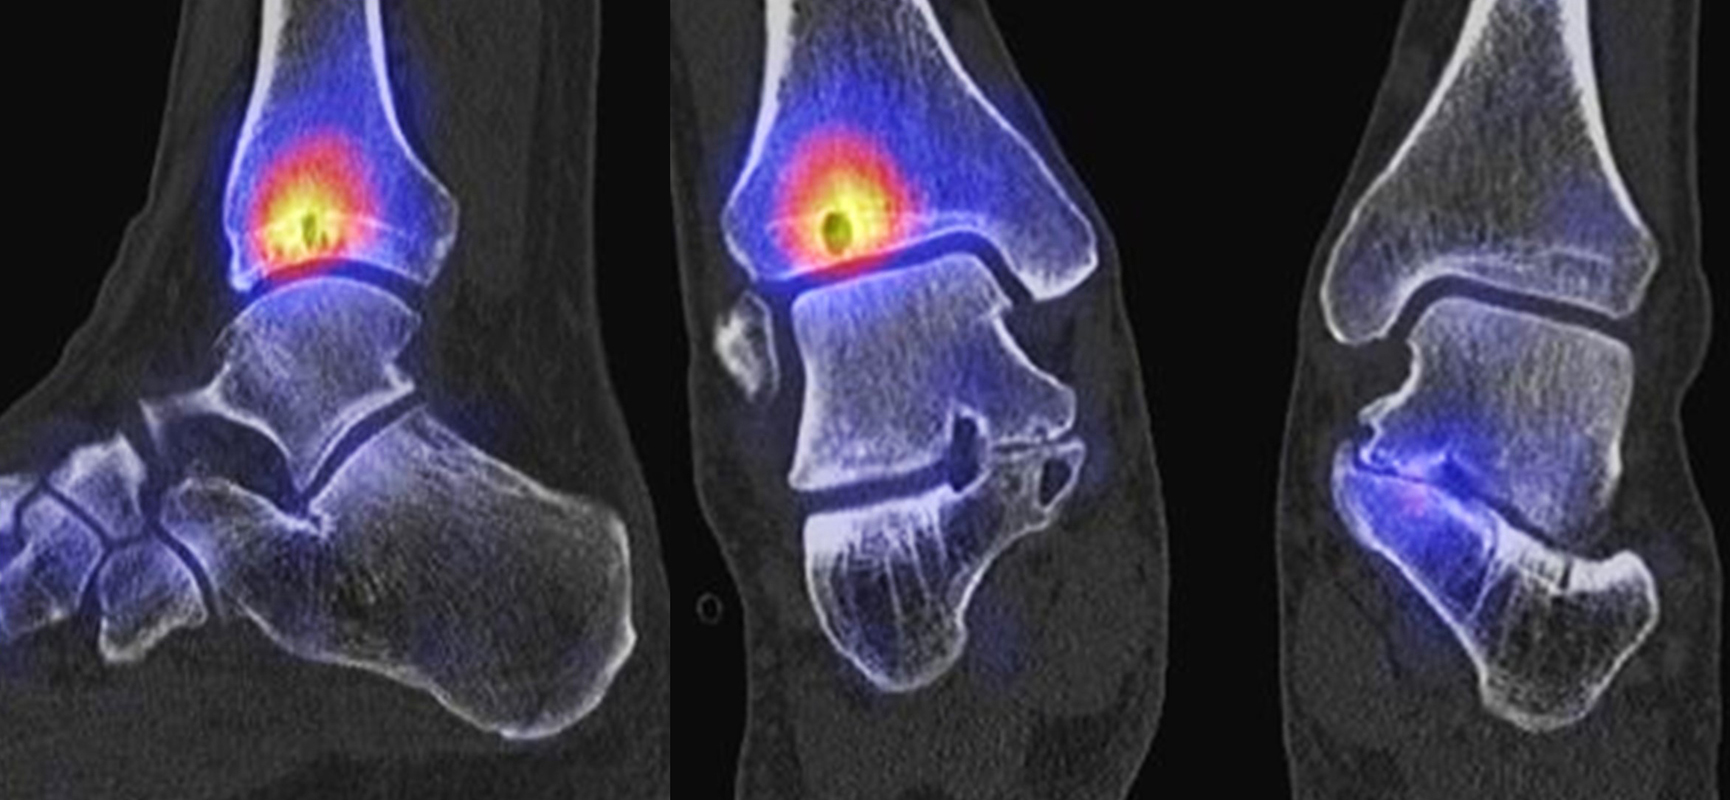

Abbildung 1.8.a und b: Akute Arthritis bei bekannter Gicht in beiden OSG: links die Früh-/Weichteilphase; rechts die Mineralisations­phase. Deutliche, entzündlich bedingte Mehranreicherungen in der Früh-/Weichteilphase. In der Mineralisation­sphase erkennt man die entzündliche Mitreaktion der subchondralen Gelenkabschnitte.

Abbildung 1.8.c - e: Akute Arthritis in beiden OSG, rechts > links. Im SPECT/CT erkennt man die Mitreaktion der subchondralen Gelenkabschnitte. Die Arthritis ist so akut, dass (noch) keine ossären morphologischen Veränderungen im CT abgrenzbar sind.

Zum Lesen der Bildbeschreibung und zur Vollansicht bitte die Bilder anklicken. Bilder: H. C. Rischke